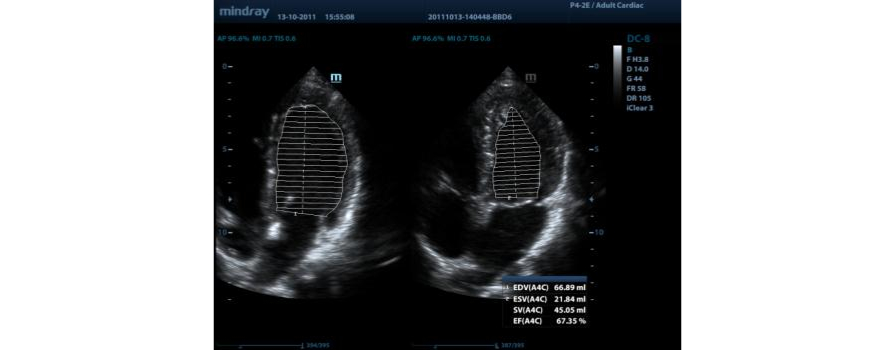

AutoEF

Diyastol/sistol ?er?eveleri otomatik olarak alg?lamak ve Simpson y?ntemiyle EDV/ESV/EF ve benzeri sonu?lar? elde etmek i?in 2 boyutlu eko g?rĂŒntĂŒlerini analiz etmenin ak?ll? bir yolu.